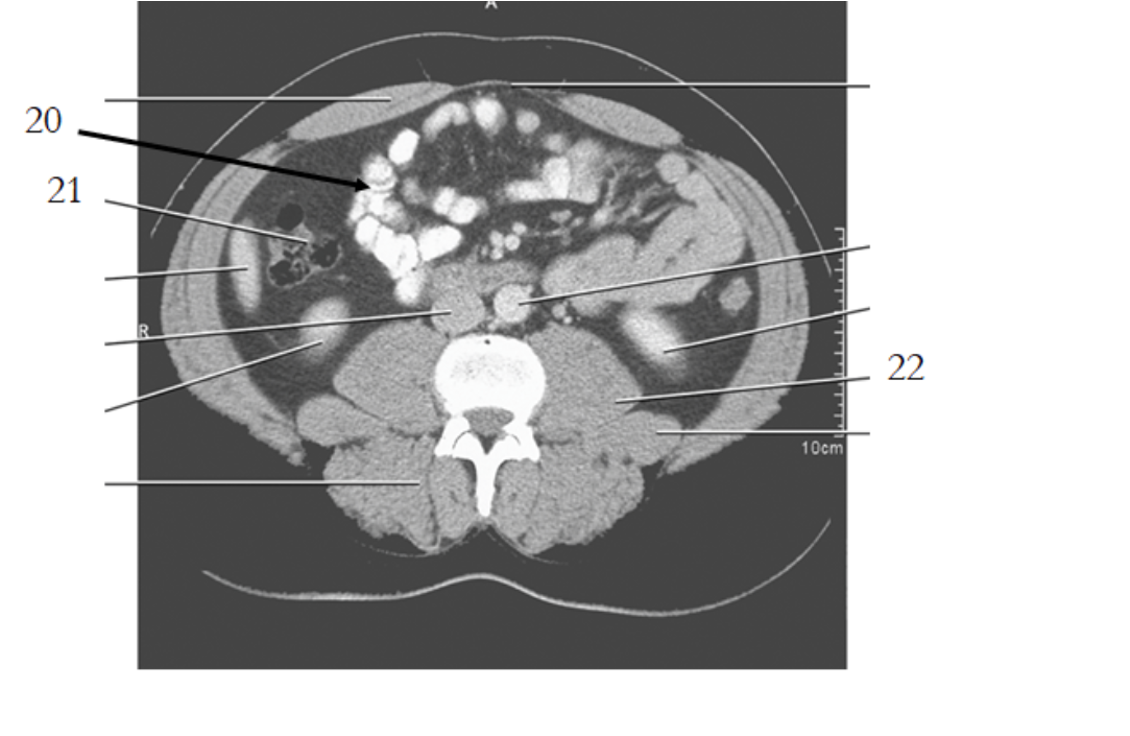

20

aorta

small bowel

21

large bowel